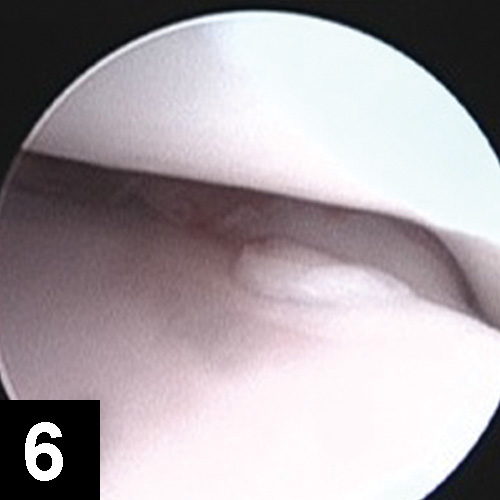

Initially, nonsurgical treatment of the primary condition (eg, weight management, analgesics, joint supplements, exercise modification, physiotherapy) can be instituted. When indicated, arthroscopy with fragment removal and abnormal cartilage debridement is recommended for fragmentation of the coronoid process in clinically affected animals that do not respond to conservative management (Figure 6).